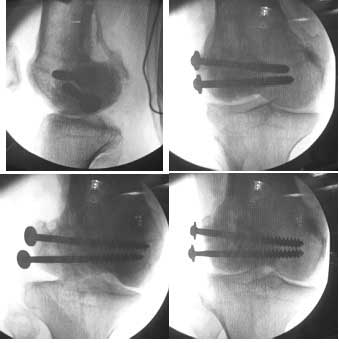

I opened it up from the lateral aspect.

Freed up the non-union site with minimal disturbance to the posterior and lateral soft tissue attachments on the lateral condyle fragment.

Applied a distractor between femoral shaft and tibia, to create a space on the lateral aspect.

This brought the lateral condylar fragment into a position that seemed to be reasonably well aligned, but showed up a bone gap.

This was fixed temporarily, bone grafted with tricortical struts, and fixed by two cancellous screws. The fragment was not large enough to afford any fixation to a plate or such implant, and the screws held it compressed well to the rest of the distal femur.

Post-op - limb is well aligned, rom 0-30, but I am not pushing that right now, for the next two or three weeks.

Further plan - hope that the screws hold the fragment appropriately till union, but if the stability on table is anything to judge by, that should not be a problem.

Pictures attached.

A good job, though personally I would have preferred the screws a bit longer.